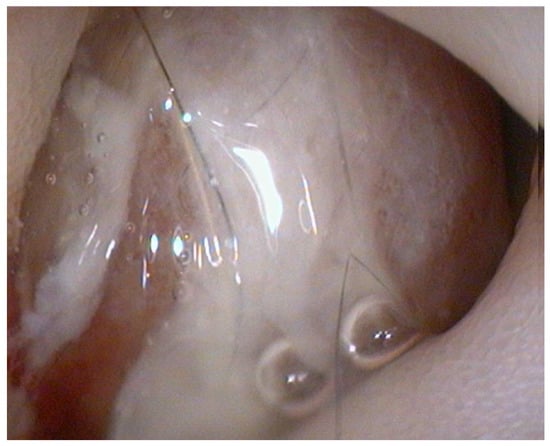

Histopathological examination of the gastric biopsies revealed mucosa with deep, hyperplastic crypts and occasional erosive and ulcerated areas replaced by necrotic and collagenous material containing abundant eosinophils, together with a mixed inflammatory infiltrate of neutrophils, small lymphocytes, and scattered eosinophils. Duodenal biopsies, including those obtained distal to the mass, showed irregular, shortened and fused villi with a moderate mixed lymphoplasmacytic infiltrate containing neutrophils and eosinophils in the lamina propria. Histopathological examination of the duodenal mass revealed a sample devoid of recognizable microanatomical architecture, composed of fibrocollagenous tissue interspersed with densely cellular areas (Figure 2). Overall, the findings were consistent with eosinophilic and fibroplastic gastroenteritis compatible with feline gastrointestinal eosinophilic sclerosing fibroplasia (FGESF).

Figure 2. Histological section of endoscopic duodenal biopsy showing dense eosinophilic infiltrates and marked fibroplasia with disrupted mucosal architecture H&E, 200×, scale bar = 200 µm.